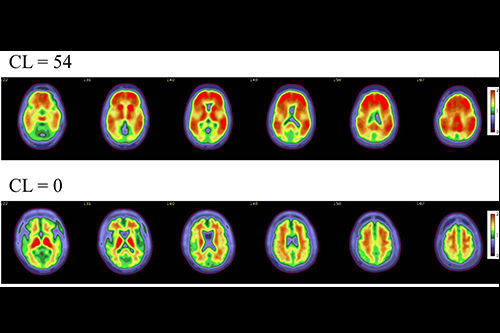

Schematic illustrates how fill states are derived. (A) Derivation of an exemplary tau fill state. Note that different meta-regions of interest (ROIs) were recommended for the assessment of amyloid PET markers from carbon-11 Pittsburgh compound B (C-11 PiB) and F-18 florbetapir The bottom beige box provides definitions for the two distinct concepts of fill states and standardized uptake value (SUV) ratios. (B) Surface plots corresponding to exemplary fill states for amyloid, tau, and neurodegeneration. The gray-shaded area indicates the meta-ROI, and the colored area indicates abnormal voxels. Color coding: blue = amyloid, purple = tau, red = neurodegeneration. Con = control. Image and caption courtesy of RSNA.